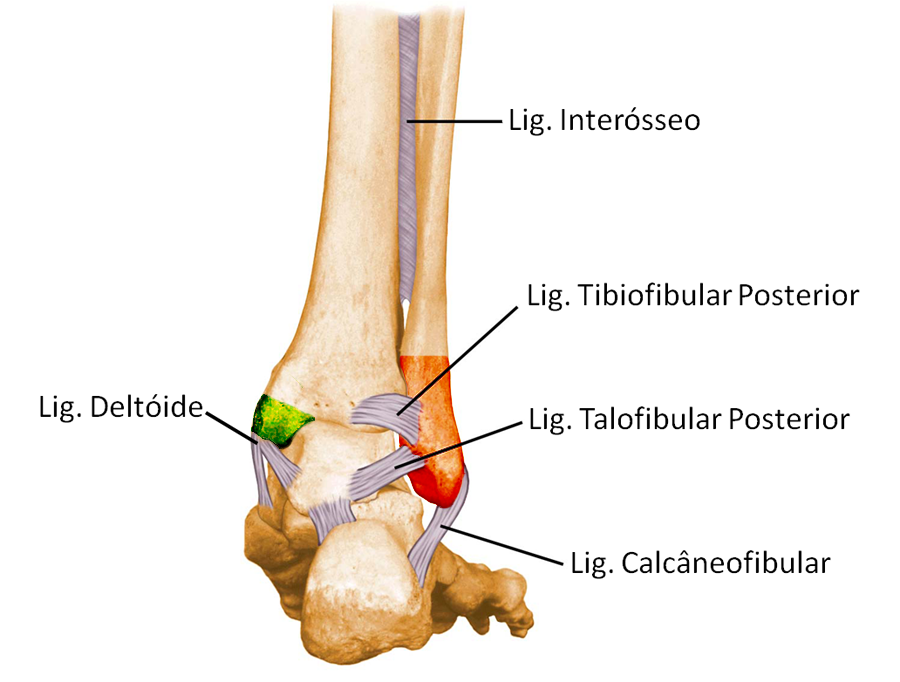

A tíbia articula-se com o tálus superiormente e medialmente através da articulação tibiotalar e a fíbula articula-se com o tálus lateralmente através da articulação fíbulotalar. Por sua vez, a tíbia e fíbula se unem através da sindesmose (articulação tibiofibular), uma articulação bastante forte e estável, presa pelos ligamentos tibiofibular anterior e posterior.

O complexo ligamentar lateral é formado por três ligamentos: o talofibular anterior (LTFA), o calcâneofibular (LCF) e o talofibular posterior (LTFP). Eles impedem que o pé exceda o movimento de inversão (para dentro) e a rotação interna. O ligamento talofibular anterior é o mais frágil e o que mais é lesionado nas entorses de tornozelo.

O ligamento da porção medial é chamado de deltóide. Possui duas camadas e impede a eversão (movimento para fora) e a rotação externa do pé. Esses ligamentos estão intimamente envolvidos com as fraturas do tornozelo e sofrem lesão e rupturas durante o trauma.